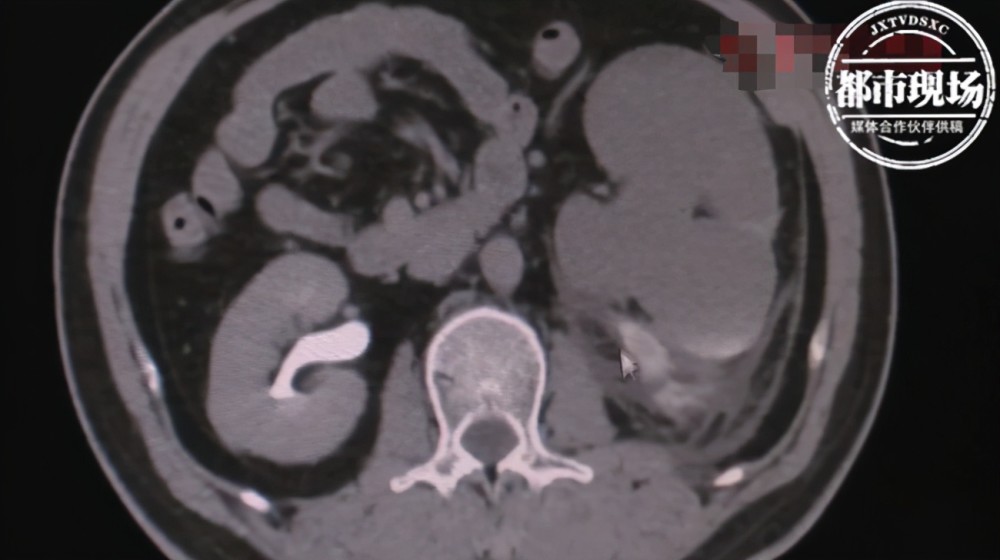

进医院检查后 , 医生发现章先生的肾脏明显比普通人要薄很多 。 医生告诉采访人员 , 章先生的输尿管肾脏有大几十颗结石 , 这就导致输尿管梗阻 , 于是肾脏产生的尿液排不出来 , 肾积水也就越来越重 , 这个时候肾脏就变得像一张纸一样薄 。

医生表示 , 这样的肾脏是无法忍受任何撞击的 , 这也是章显示肾脏破裂的主要原因 。 不过 , 幸运的是章先生肾脏破口并不太大 。 医生通过开刀做开放性手术修复 , 进行引流后 , 伤口就会自己慢慢地愈合 。